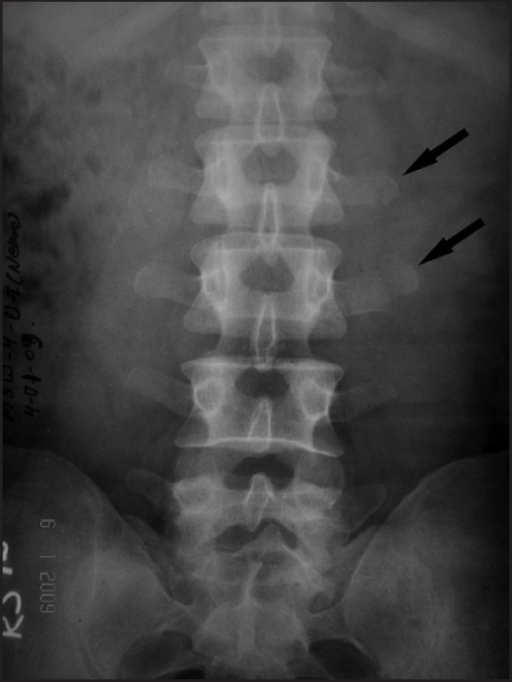

Isolated transverse process fracture of the lumbar vertebrae. Agrawal A, Srivastava S, Kakani A - Journal of emergencies, trauma, and shock (2009)

| current | 21:54, 19 October 2022 | 512 × 682 (247 KB) | Rossdonaldson1 (talk | contribs) | Isolated transverse process fracture of the lumbar vertebrae. Agrawal A, Srivastava S, Kakani A - Journal of emergencies, trauma, and shock (2009) |